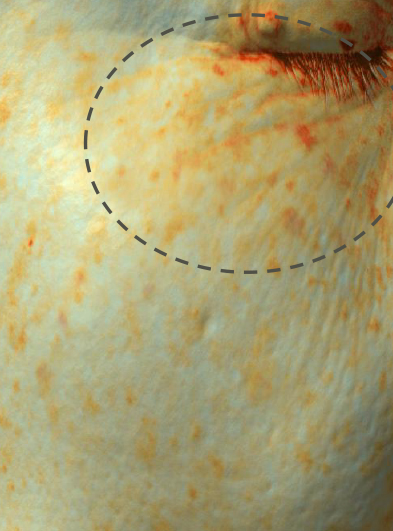

page_tranexamic_11